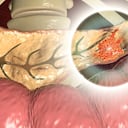

Uno de los órganos más importantes del cuerpo humano es el páncreas, el cual de acuerdo con el Instituto Nacional del Cáncer, produce los jugos pancreáticos que contienen enzimas que pueden ayudar a facilitar la digestión y a elaborar hormonas, incluso la insulina.

Es por esto que una de las enfermedades más comunes de este órgano es la pancreatitis, que según la el National Institute of Diabetes and Digestive and Digestive and Kidney Diseases, es una inflamación del órgano que puede ser aguda apareciendo de manera repentina, teniendo una duración a corto plazo y que se puede solucionar con días de tratamiento médico; De igual manera, también puede ser crónica teniendo un tiempo más largo de duración y puede causar un daño más permanente.